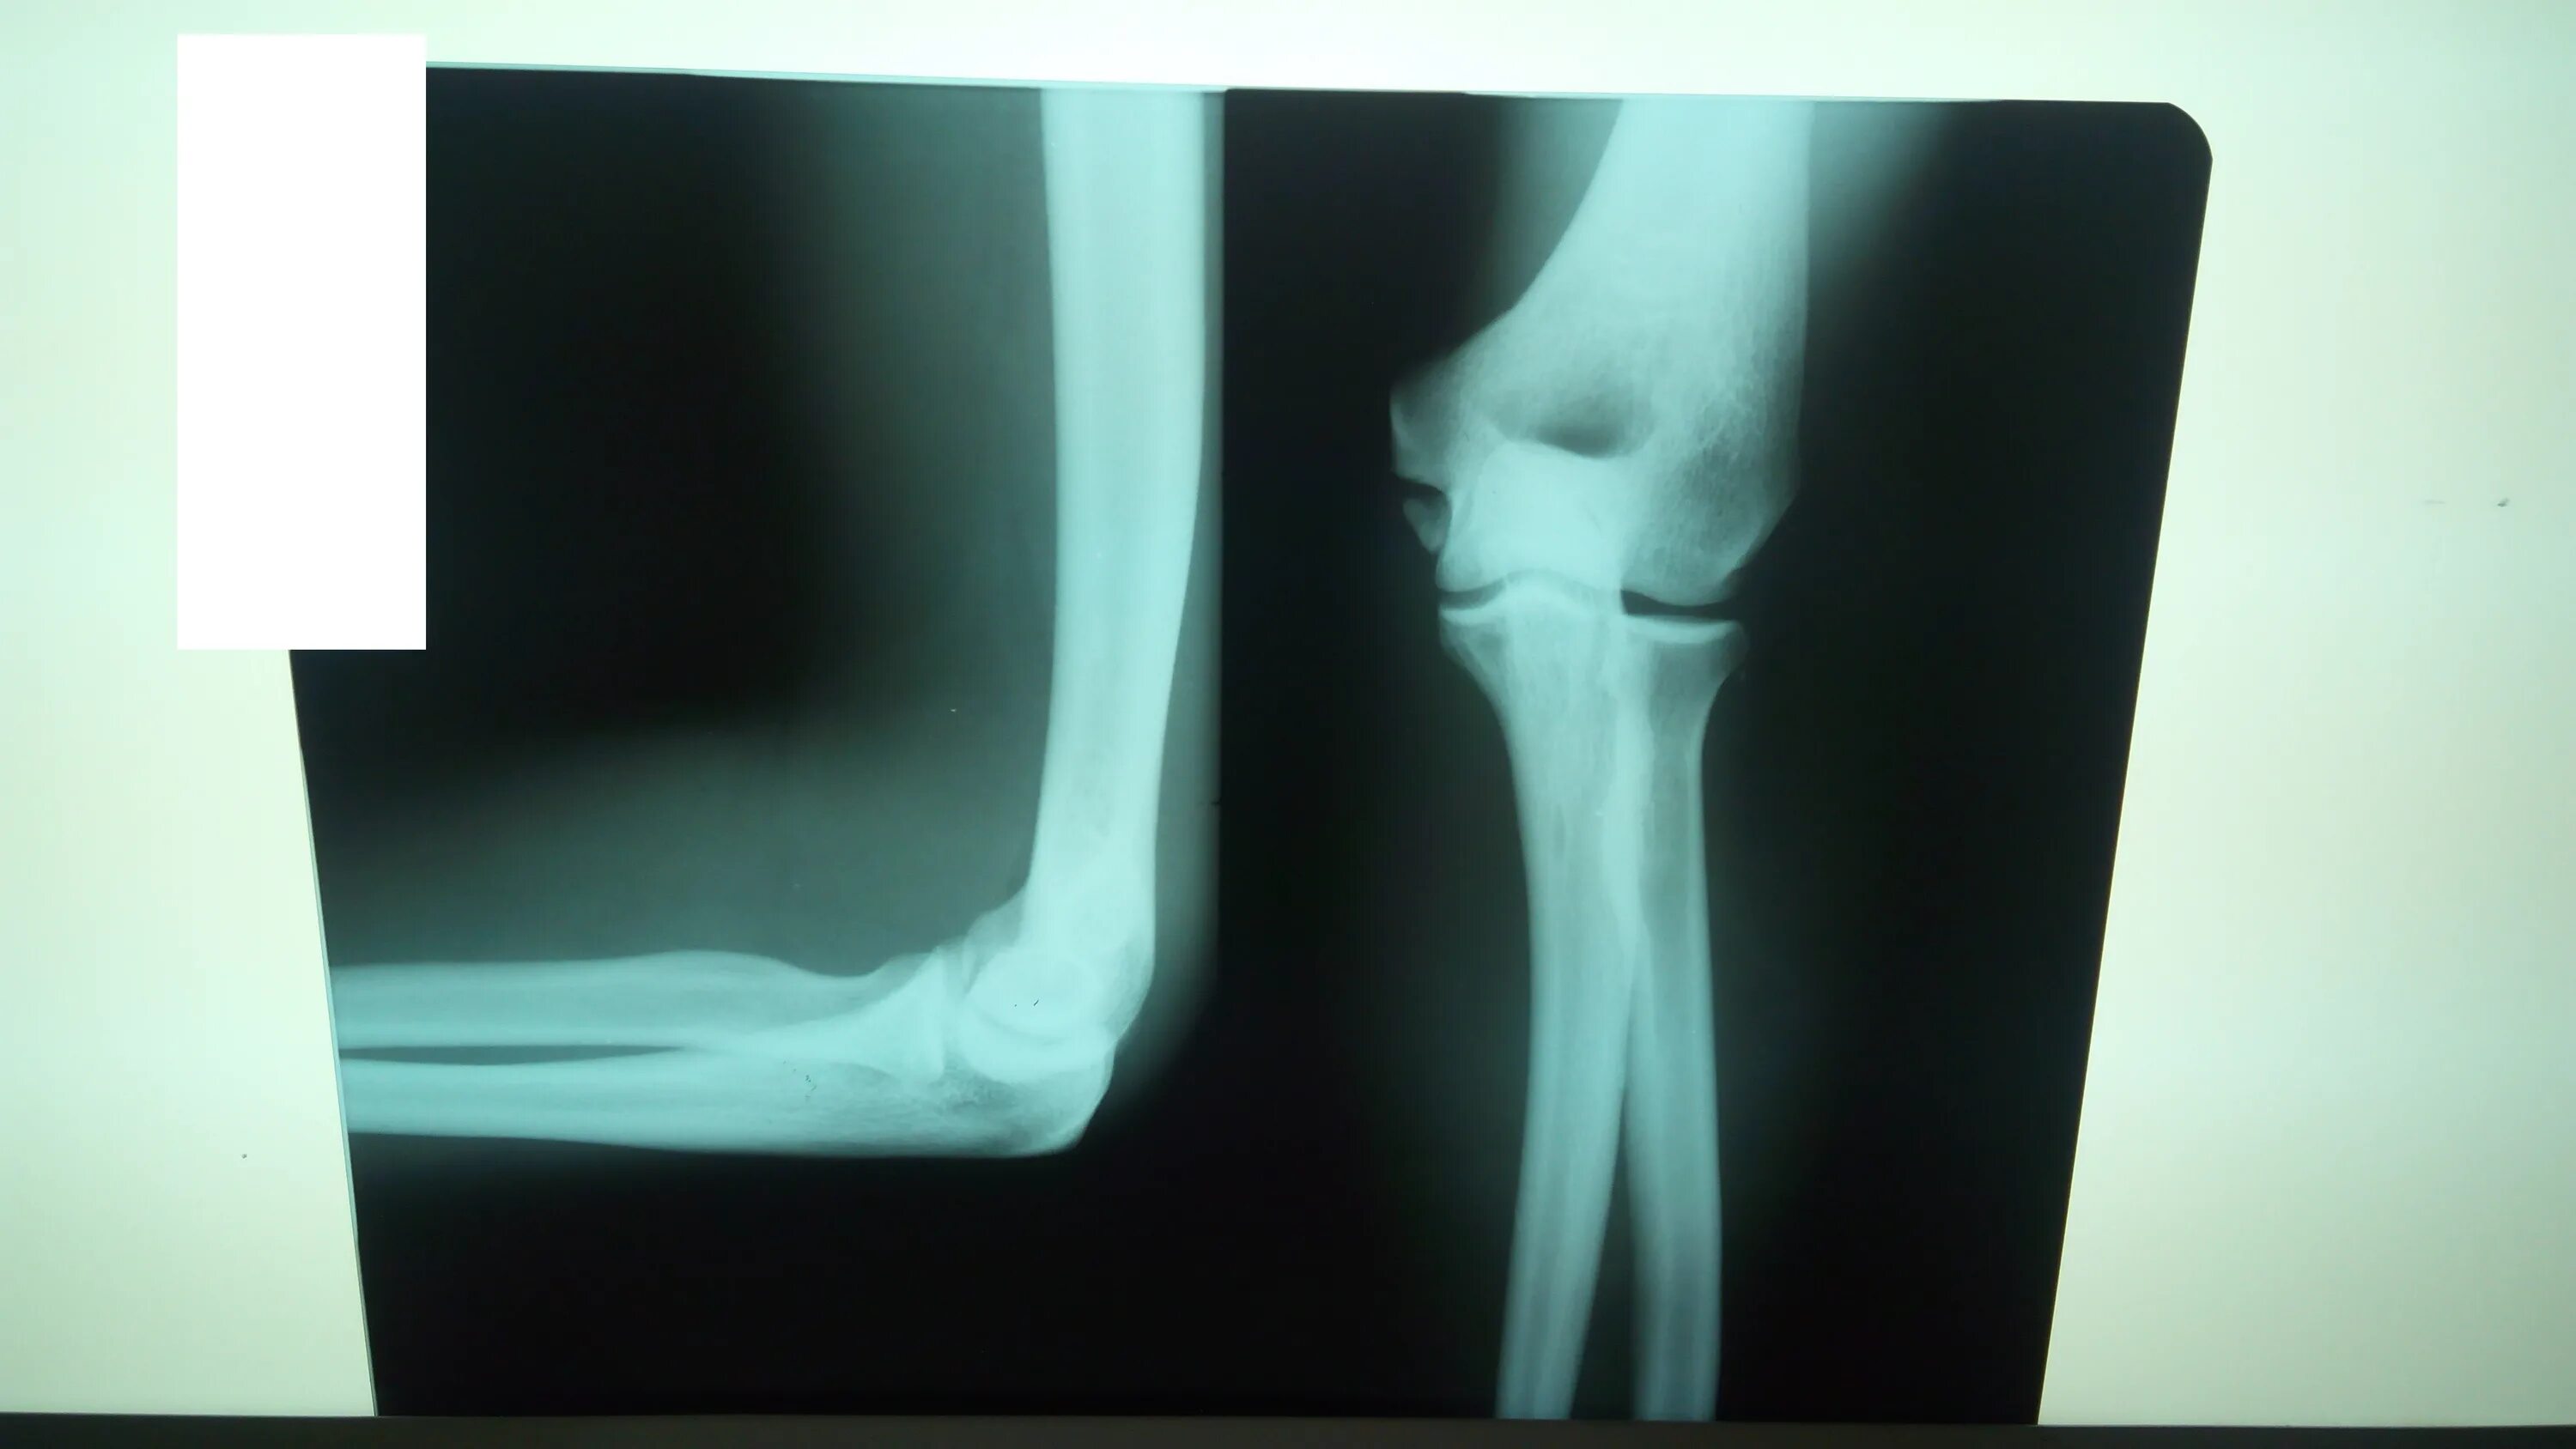

Мкб 10 ушиб локтевого сустава